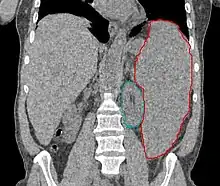

- Splenomegaly or rarely hepatomegaly